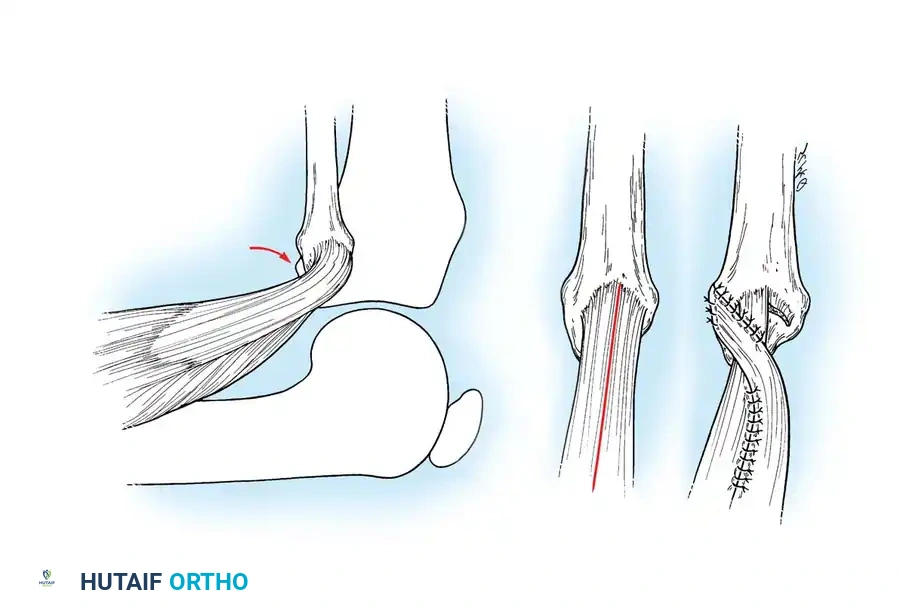

Extraarticular snapping on the lateral aspect of the knee is most frequently attributed to an abnormal anterior insertion of the biceps femoris tendon on the fibular head. During knee flexion and extension, the anomalous tendon slips over the prominent fibular head, creating a palpable and audible snap.

If conservative management (activity modification, hamstring stretching, NSAIDs) fails, surgical realignment is indicated. Kristensen et al. and Lokiec et al. have demonstrated excellent outcomes with surgical reinsertion.

Surgical Technique: Biceps Femoris Rerouting

- Positioning: Supine with a bump under the ipsilateral hip to allow internal rotation of the leg.

- Incision: Make a longitudinal incision over the posterolateral aspect of the knee, centered over the fibular head.

- Dissection: Carefully identify and protect the common peroneal nerve, which courses posterior to the biceps femoris tendon and wraps around the fibular neck.

- Tendon Management: Identify the anomalous anterior insertion of the biceps femoris. Divide the anterior half of the tendon.

- Reattachment: Reroute and suture the divided tendon back over the posterolateral aspect of the fibular head, effectively covering the bony hump and preventing the anterior subluxation mechanism.

- Alternative: If the fibular head is excessively prominent, a partial resection of the fibular head (fibulectomy) with subsequent reattachment of the tendon and lateral collateral ligament (LCL) may be performed.